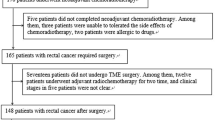

Figure 1 shows the identification, eligibility, and inclusion of patients in the study. A total of 55 patients were selected from initial identification of 83 patients after exclusion of patients who underwent other therapies before MRI (n = 13), those where more than 1 week had passed between MRI and NAC (n = 2), those with severe image artifacts (n = 5), incomplete NAC (n = 6), and those with no surgical resection after NAC (n = 2).